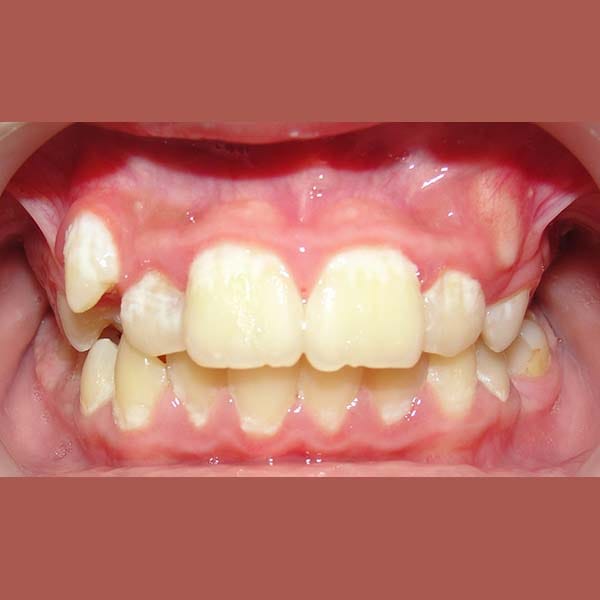

BEFORE

This young woman suffered from an upper jaw stenosis, crowded teeth, and the absence of one of the upper molars.

She was treated with Daimon braces (an orthodontic device that doesn’t require rubber to fix the archwires, which reduces friction and speeds up treatment).

At the end of the treatment, we were able to see a clear expansion in her upper jaw, her teeth were aligned beautifully, and the gap resulting from the absence of the molar was closed orthodontically.